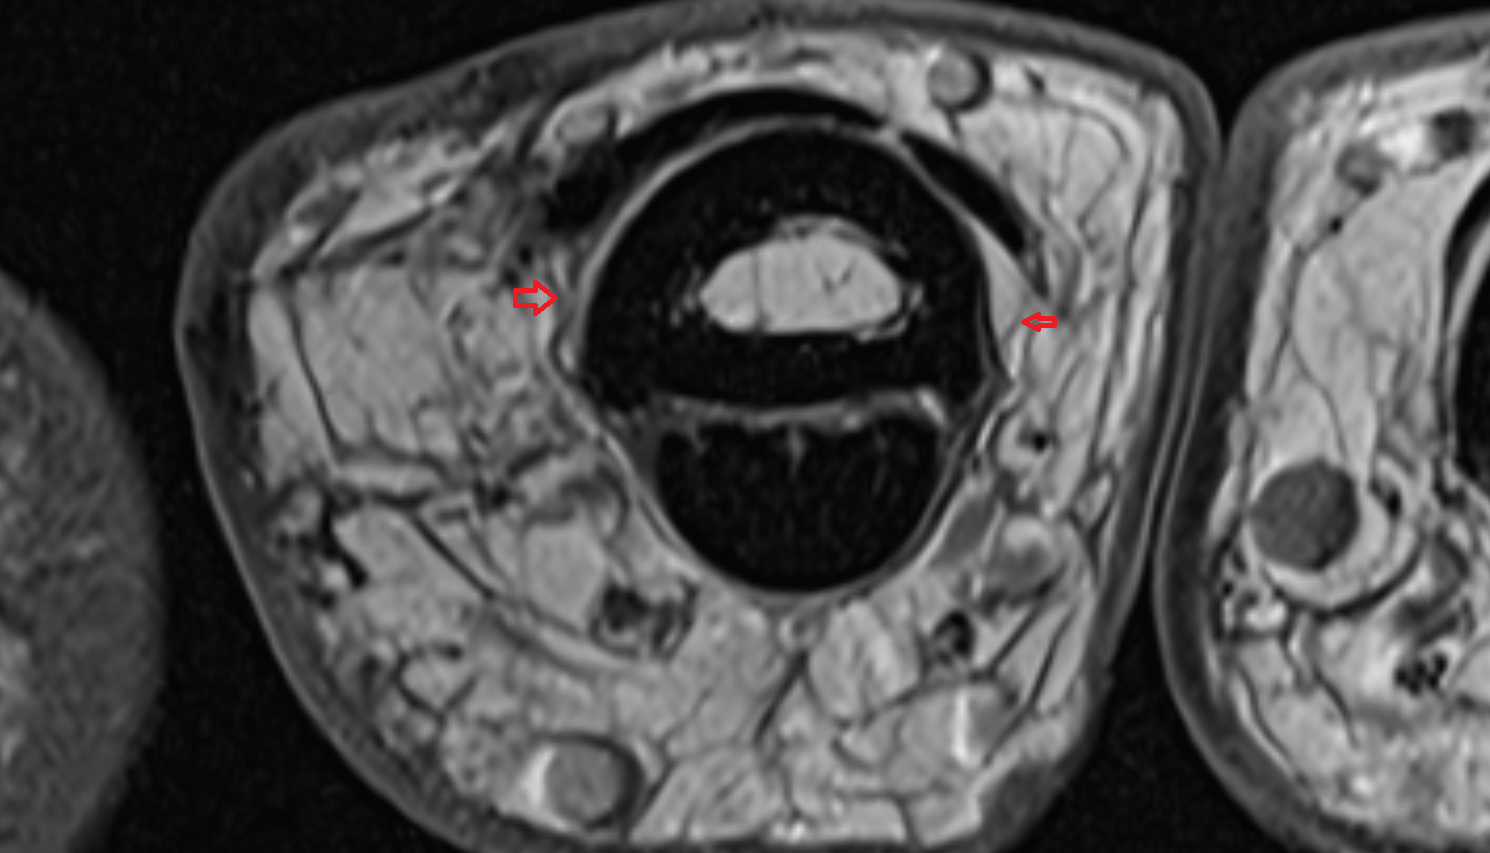

- Peripheral zone of prostate

- Anterior Fibromuscular Stroma of prostate

- Central zone of prostate

- Transitional zone of prostate